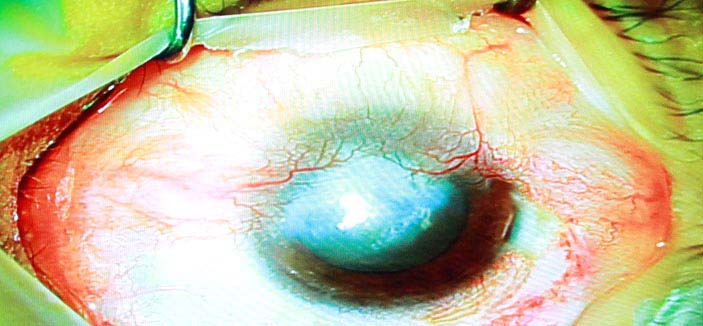

ترشيح المملكة لتكون بداية انطلاق جمعية الشرق الأوسط للقرنية برئاسة د. الطويرقي

«الجزيرة» تقف على إجراء أول عمليات زراعة الخلايا الجذعية بتخصصي الملك خالد للعيون        1 / 6 Showing image 1 of 6   الجزيرة - علياء الناجي: الجزيرة - علياء الناجي: في سابقة هي الأولى من نوعها، تقف وسائل الإعلام على أُولى عمليات زراعة الخلايا الجذعية في المملكة. وقد وقفت «الجزيرة» على إجراء العملية وزراعة الخلايا الجذعية لمريض يعاني من اعتلال بقرنيته. ووفقاً للدكتور آشلي بيرنز المدير الطبي التنفيذي بمستشفى الملك خالد التخصصي للعيون خلال تصريحه إلى «الجزيرة»، توجد دراسات مستقبلية لعلاج «الشبكية» بالخلايا الجذعية؛ إذ إنها حالياً تعالج القرنية فحسب. وأكد الدكتور بيرنز أنه يتوقع مستقبلاً أن تكون الخلايا الجذعية لعلاج أمراض عدة، مشيراً إلى وجود 100 حالة حالياً على قائمة الانتظار بالمستشفى، والمختبر الذي افتتح مؤخراً سيسهم بدوره في نقلة نوعية لعلاج القرنية بالخلايا الجذعية. وفي ظل الإنجازات المتوالية التي يحققها مستشفى الملك خالد التخصصي للعيون في زراعة القرنيات وزراعة الخلايا الجذعية، فقد تم إعلان إنشاء جمعية الشرق الأوسط للقرنية، وتم اختيار الدكتور عبدالإله بن عباد الطويرقي المدير العام التنفيذي لمستشفى الملك خالد التخصصي للعيون رئيساً لها نظراً لمكانة المستشفى العالمية، والتطور الموجود فيه، وكذلك مواكبة كل جديد في طب العيون وعدد وكفاءة عمليات القرنية والبدء في عمليات زراعة الخلايا الجذعية للقرنية وما يحظي به المستشفى من كوادر طبية وبحثية. والجمعية مفتوحة لانضمام الأطباء لها، إضافة لمجموعة الأساتذة الذين أعلنوا تأسيس هذه الجمعية. وتوجد جمعيات مماثلة في أمريكا وآسيا وأمريكا اللاتينية، الهدف منها هو تطور طب وجراحة القرنية، والتواصل مع الجمعيات المماثلة حول العالم، ودمجها تحت جمعية واحدة. وبيَّن «الطويرقي» قبول رئاسة هذه الجمعية لرفع مكانة المملكة عالمياً وإظهار ما لديها من تقدم طبي وتعليمي وبحثي في طب العيون، وذلك تزامناً مع بدء عمل مختبر الخلايا الجذعية. والأطباء الذين أعلنوا ترشيح د. الطويرقي هم الدكتورة جنيفر إيليسيف أستاذة طب العيون ومديرة مركز هندسة الأنسجة بمعهد ويلمر بجامعة جونز هوبكنز الطبية من الولايات المتحدة الأمريكية، ومن البرازيل الدكتور جوس جومنيز مدير قسم الشدفة الأمامية بجامعة ساو باولو، ومن الهند الدكتور فرندر سنجوان مدير مركز إعادة بناء سطح العين بحيدر إباد، ومن الأرجنتين الدكتور دانيل سوكورستي أستاذ ورئيس قسم طب العيون بكلية الطب بجامعة سلفادور ببوينس آيرس. من جهته، أكد الدكتور عبدالإله بن عباد الطويرقي المدير العام التنفيذي لمستشفى الملك خالد التخصصي للعيون أنه تم إجراء أول ثلاث عمليات زراعة الخلايا الجذعية للقرنية، الأولى لرجل يبلغ من العمر 58 عاماً، والثانية لشاب 28 عاماً، والثالثة لطفلة عمرها 10 أعوام، وجميعهم سعوديون، وكانت العمليات منقولة على الهواء مباشرة لقاعة المحاضرات الرئيسية بالمستشفى. وأضاف د. الطويرقي بأنه تم أخذ عينة من خلايا القرنية للمريض قبل أسبوعين، وقمنا بمتابعتها يومياً في المختبر الخاص بالخلايا الجذعية حتى نمت، وتم بعدها إخضاع المريض المستفيد للجراحة، والحمد لله تكللت العملية بالنجاح بفضل الله، وهذا الإنجاز الطبي متميز على مستوى الشرق الأوسط، ونحن سعداء بأن يضاف مثل هذا الإنجاز لاسم مملكتنا الحبيبة. وقال الدكتور الطويرقي إن نتائج العملية ستكون بعد أسبوعين تقريباً من اليوم، وإن شاء الله النتائج مبشرة. وأضاف: المستشفى بحسب مكانته المتميزة بين مستشفيات العيون في العالم لديه بنك العيون الذي يعتبر فريداً من نوعه، ليس في المملكة فحسب بل في الشرق الأوسط كافة. ومختبر الخلايا الجذعية للقرنية الأول من نوعه في الشرق الأوسط، وهو موجود في بعض الدول الأوروبية واليابان وبعض دول أمريكا اللاتينية. |